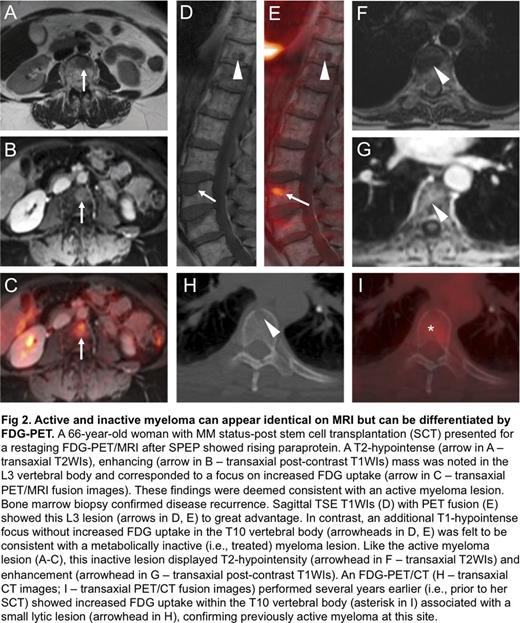

Among 15 patients with new clinical diagnoses of MM, 9 (60%) had FDG-avid bone lesions. In contrast, among the 10 patients with new clinical diagnoses of MGUS or SMM, none had FDG-avid bone lesions. Of the remaining 11 patients imaged for suspected recurrence or surveillance of previously treated MM, only 4 had FDG-avid bone lesions. Analysis of 20 FDG-avid bone lesions imaged on the same day with both PET/CT and PET/MRI revealed CT correlates for 15 lesions (75%) and MRI correlates for 14 lesions (70%). Notably, there were 5 spinal lesions in a single patient that had CT correlates without MRI correlates; however, no sagittal TSE T1WIs of the spine were acquired, reducing the sensitivity of MRI. Five of these 20 FDG-avid bone lesions were apparent on MRI but not CT (Fig 1). Using marrow biopsy and/or serum protein electrophoresis (SPEP) as a standard of reference, FDG-PET correctly differentiated metabolically active from inactive disease in 6 of 8 patients with previously treated MM. Active and inactive lesions were otherwise indistinguishable on MRI alone; both lesion types generally exhibited focal T2-hyperintensity and enhancement (Fig 2).

FDG-PET/MRI is feasible for both the initial staging and subsequent treatment response assessment of PCDs. To maximize the clinical utility of PET/MRI relative to PET/CT for the anatomic depiction of marrow-replacing lesions, TSE T1WIs should be incorporated into standard protocols, especially for the spine and pelvis. The addition of FDG-PET to whole-body MRI is useful for differentiating metabolically active and inactive disease, which can look identical on MRI alone. PET/MRI also provides substantial radiation dose reductions relative to PET/CT, especially in patients with malignancies such as MM that require frequent follow-up imaging studies (Schafer et al., Radiology, 2014). Finally, new PET tracers under development, such as those targeting VLA-4, may further expand the role of PET/MRI in PCDs by improving sensitivity for early or limited disease (Soodguptaet al., JNM, 2016).